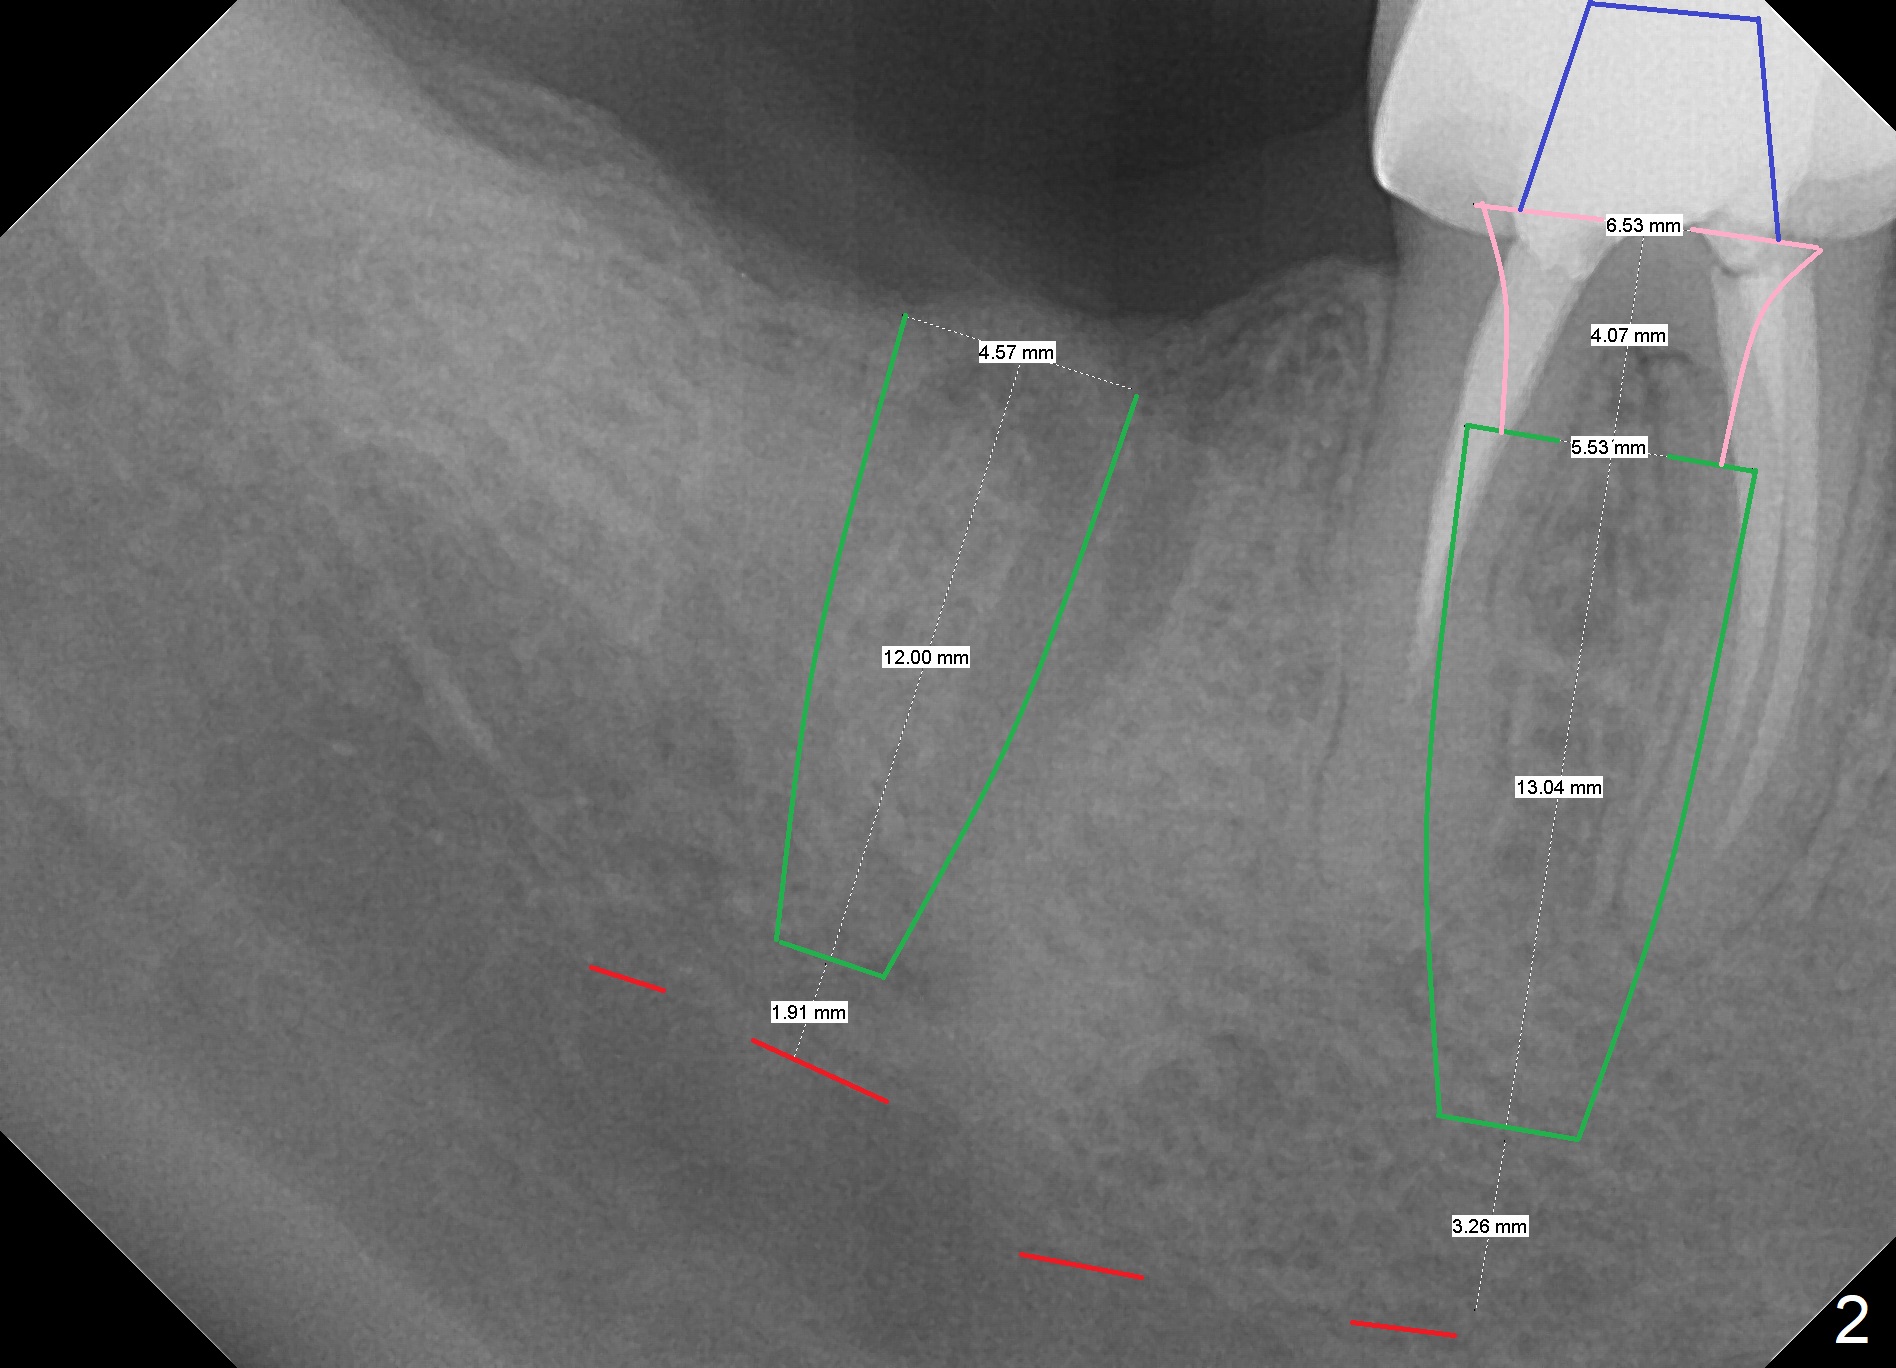

To quicken healing, an implant larger than 5.5 mm will be placed (Fig.2). To establish osteotomy in the relative narrow septum, it seems necessary to use Magic Drills sequentially instead of single fashion. Use of 4.8 mm MD in the pointed septal crest may create vibration and instability. The drill may drift into the mesial or distal socket.